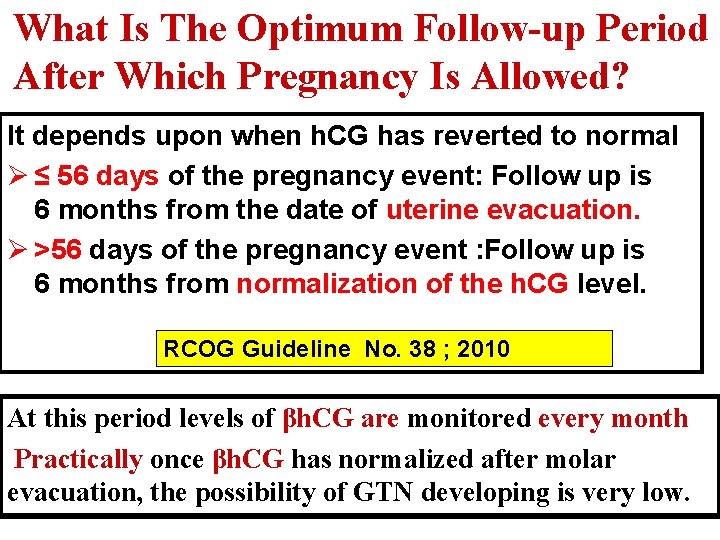

What Is The Optimum Follow-up Period Following Normalization of β h. CG? A. For 6 months from the date of uterine evacuation. B. For 6 months from normalization of the β h. CG level. C. For 12 months from the date of uterine evacuation. B

What Is The Optimum Follow-up Period After Which Pregnancy Is Allowed? It depends upon when h. CG has reverted to normal Ø ≤ 56 days of the pregnancy event: Follow up is 6 months from the date of uterine evacuation. Ø >56 days of the pregnancy event : Follow up is 6 months from normalization of the h. CG level. RCOG Guideline No. 38 ; 2010 At this period levels of βh. CG are monitored every month Practically once βh. CG has normalized after molar evacuation, the possibility of GTN developing is very low.